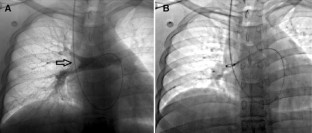

Fig. 2